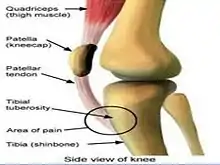

| The site of the osg and sjs on the knee: OSG at tibial tuberosity and SLJ at inferior pole of patella | |

Sinding-Larsen and Johansson syndrome,[1] named after Swedish surgeon Sven Christian Johansson (1880-1959),[2] and Christian Magnus Falsen Sinding-Larsen (1866-1930),[3] a Norwegian physician, is apophysitis of the inferior pole of the patella. It is analogous to Osgood–Schlatter disease which involves the upper margin of the tibia. This variant was discovered in 1908, during a winter indoor Olympic qualifier event in Scandinavia. Sever's disease is a similar condition affecting the heel.

The condition is usually seen in athletic individuals typically between 10 and 14 years of age. Following a strain or partial rupture of patellar ligament the patient develops a traction ‘tendinitis’ characterized by pain and point tenderness at the inferior (lower) pole of the patella associated with focal swelling.